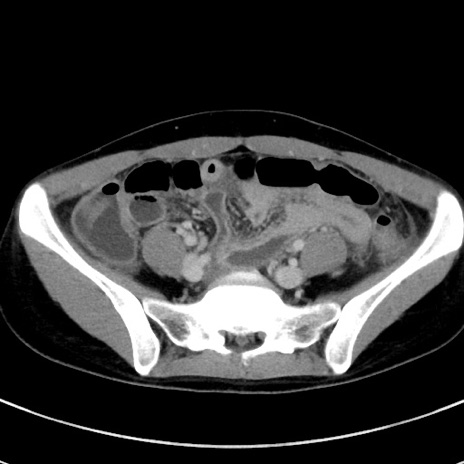

症例17(横断像)

【症例】20歳代女性

【主訴】嘔吐、下腹部痛

【現病歴】昨日夕食後に嘔吐し下腹部痛が出現。本日になっても嘔吐持続し改善しないため来院。

【身体所見】意識清明、BT 37.2℃、BP 108/67mmHg、腹部:平坦、やや硬、下腹部正中から右にかけて圧痛あり、反跳痛軽度あり、tapping pain(+)。

【データ】WBC 13600、CRP 14.94